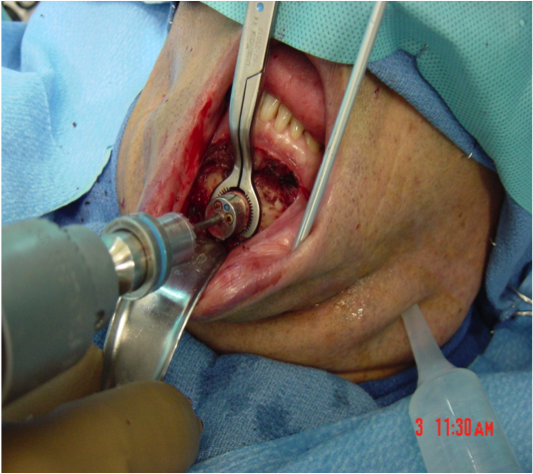

This procedure places tension on the tongue, limiting the posterior from shifting during sleep. The procedure starts with a small incision made inside the lower lip. Then, the surgeon moves away all the soft tissue to expose the lower jaw. Small rectangular cuts are then made in the lower jaw directly in front of the lower front teeth. This area attached to the genioglossus muscle is then moved forward and turned slightly. To hold this bone fragment in place, the surgeon puts in a titanium screw to immobilize it.

The photos on this website are from real surgeries performed by Dr. Ulloa. Due to the

graphic nature of the images and content, viewer discretion is advised.